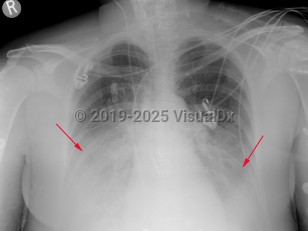

Imaging Studies image of Legionellosis - imageId=2954652. Click to open in gallery.  caption: 'Frontal chest x-ray with opacities in the bilateral lower lobes in this patient with Legionnaires' disease.'

Frontal chest x-ray with opacities in the bilateral lower lobes in this patient with Legionnaires' disease.